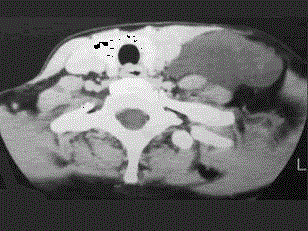

问题 37岁女性,左侧颈部肿块渐进性增大,无压痛,局部皮温不高,CT、MRI扫描如图所示,请选择正确的描述或诊断 ( )

选项 A、MRI的TWI呈高信号,其内可见分隔 B、考虑为淋巴管囊肿 C、增强扫描未见强化 D、MRI的TWI呈低信号 E、CT发现左侧颈后三角区可见低密度肿块影

答案 ABCDE